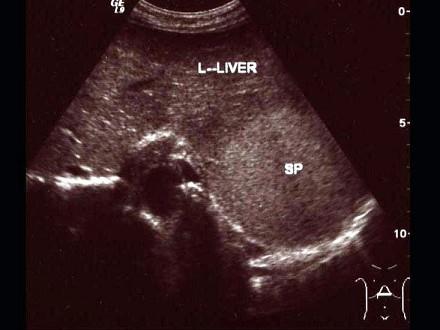

问题 超声示意图为一患者剑突下横切图,显示了肝脾叠影图像,下列哪些患者最可能出现这种现象?()

选项 A.慢性活动性肝炎 B.慢性粒细胞白血病 C.急性乙型肝炎 D.肝脓肿 E.胃癌

答案 AB